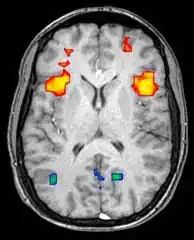

Функциональная магнитно-резонансная томография

Функциональная магнитно-резонансная томография (фМРТ) основана на парамагнитных свойствах оксигенированого и дезоксигенированого гемоглобина и дает возможность увидеть изменения кровообращения головного мозга в зависимости от его активности. Такие изображения показывают, какие участки мозга активированы (и каким образом) при исполнении определённых заданий.

Большинство фМРТ-томографов дают возможность представлять исследуемому разные визуальные изображения, звуковые и тактильные стимулы и производить действия типа нажатия кнопки или движения джойстиком. Следовательно, фМРТ можно использовать, чтобы показывать структуры мозга и процессы, связанные с восприятием, мышлением и движениями. Разрешение фМРТ на данный момент 2—3 мм, ограниченное кровоснабжением, влияющим на нейрональную активность. Она существенно заменяет ПЭТ при исследовании типов активации головного мозга. ПЭТ, однако, одерживает значительное преимущество, будучи в состоянии идентифицировать специфические клеточные рецепторы или (моноаминовые трансмиттеры) связанные с нейромедиаторами, благодаря визуализации меченных радиоактивно рецепторных «лигандов» (рецепторный лиганд — химическое вещество, связанное с рецептором).

фМРТ используют как для медицинских исследований, так и (всё шире) в диагностических целях. Так как фМРТ исключительно чувствительна к изменениям кровообращения, она очень хорошо диагностирует ишемию, как например при инсульте. Ранняя диагностика инсультов всё важнее в неврологии, так как медикаменты, растворяющие свернувшиеся сгустки крови, можно использовать в первые несколько часов и при определённом типе инсульта, в то время как они могут быть опасными при дальнейшем использовании. фМРТ в таких случаях дает возможность принять правильное решение.